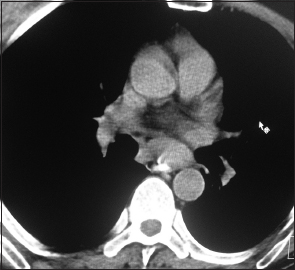

A 52 year-old nonsmoker, alcoholic male patient with spinocerebellar ataxia as comorbidity, presented in November 2016, with a complaint of progressive dysphagia of 2 months duration. Upper gastrointestinal endoscopy showed circumferential growth in lower-third of the esophagus with luminal narrowing. Computed tomography (CT) of thorax showed 13-mm thick circumferential mural thickening involving long segment of the lower esophagus causing marked luminal narrowing [Figure 1]. There was 3.5 cm × 2.5 cm mass in the subcarinal region, compressing esophageal lumen along with the few perigastric nodes [Figure 2]. Positron-emission tomography (PET)-CT showed intense fluoro-deoxy-glucose (FDG) avid thickening in the lower third of esophagus with FDG avid lower paratracheal, subcarinal, and perigastric nodes. Biopsy from the esophagus was done which was suggestive of moderately differentiated squamous-cell carcinoma [Figure 3]. The patient received neoadjuvant chemoradiation with 41.4Gy/23#/5 weeks by 3D-conformal radiation therapy technique along with five cycles of chemotherapy with injection paclitaxel 60 mg/m2 and injection carboplatin area under the curve 2 weekly. There was significant response to the treatment. Subsequently, the patient underwent thoracoscopic esophagectomy with gastric pull with feeding jejunostomy in February 2017. Histopathology showed minimal residual squamous-cell carcinoma of the esophagus with subcarinal node showing features of neuroendocrine tumor [Figure 4]. Subsequently, immunohistochemistry (IHC) was done to confirm the histopathological findings. IHC in esophageal blocks showed strong positivity for CK 5/6 [Figure 5], P63 [Figure 6], and epithelial membrane antigen [Figure 7] in tumor and surface epithelium with Ki67-30% [Figure 8], suggestive of residual small focus of squamous-cell carcinoma. IHC on subcarinal node was negative for CK5/6 and P63, strongly positive for synaptophysin [Figure 9] plus chromogranin [Figure 10], and weekly positive for CK7 [Figure 11], CK20 [Figure 12], and CDX2 [Figure 13]. Ki67 index was 4% [Figure 14], overall suggestive of atypical carcinoid tumor. There was no symptom related to endocrine overactivity or carcinoid syndrome. Follow-up PET-CT was normal, and hence the patient was kept on close follow-up, but at the time of writing the paper, the patient was untraceable.

| Figure 2 Computed tomography of thorax coronal view showing large subcarinal node